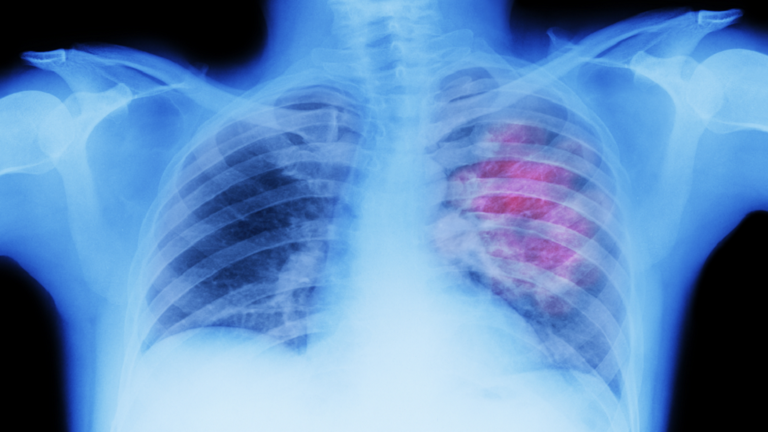

كشف خبراء أن المرضى المصابين بنوع قاتل من سرطان الرئة سيستفيدون من دواء يُعتبر أكبر اختراق علاجي منذ عقود.

ويعرف Sotorasib بأنه قرص يومي ثبت أنه يقلص الأورام لدى نصف المرضى المصابين بسرطان الرئة المتقدم غير الناتج عن التدخين. وهذا النوع، الذي يصيب واحدا من كل ثمانية مصابين بسرطان الرئة، ناتج عن طفرة في الجين المعروف باسم KRAS. وهو شكل مميت من السرطان بشكل خاص، حيث لا تكون العلاجات الحالية فعالة إلا في حوالي 10% من المصابين به.